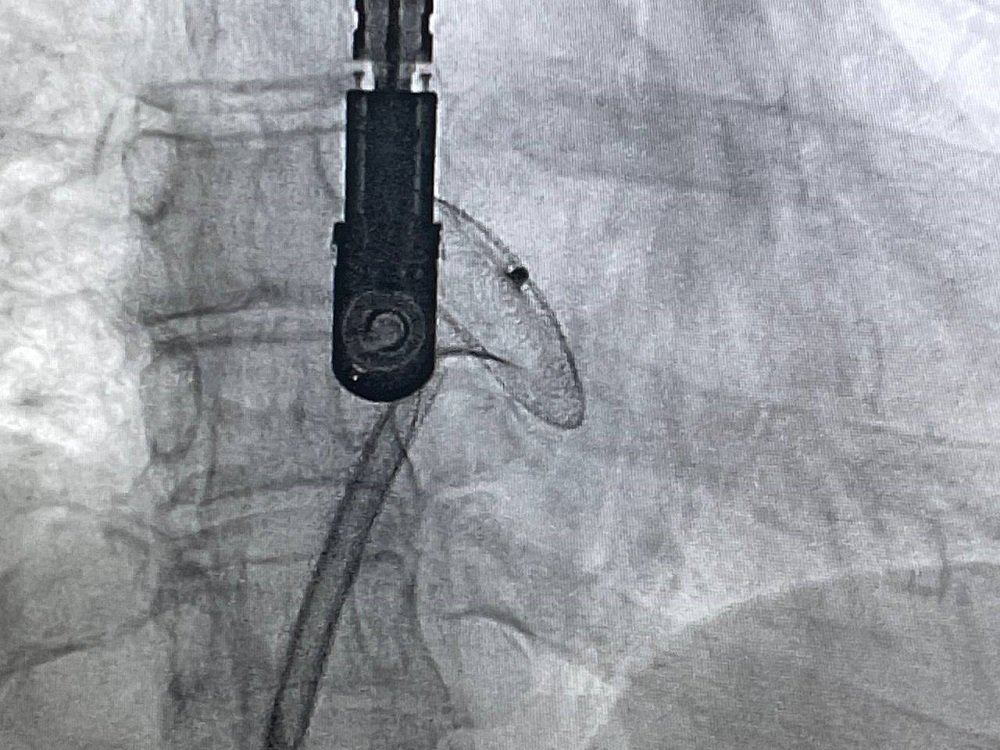

Корекція вади серця проводилась ендоваскулярно. Через прокол у стегновій судині встановили оклюдер – серцевий імплант, який у складеному стані через катетер провели до передсердя і там розкрили, надійно закривши отвори у перетинці.